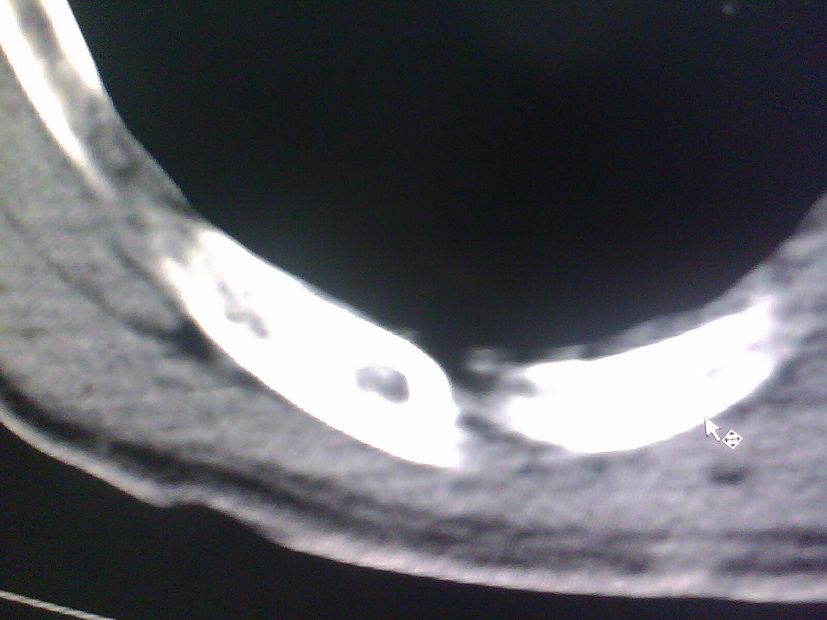

患者,男性,41y,外伤病号,来拍片,发现右侧第9后肋,肋骨膨大,有密度不均,想问大家,是否有问题,要考虑什么东西,谢谢

右侧第九后肋骨纤维结构不良。

考虑骨纤维异常增殖症(混合型)。

肋骨是骨纤好发部位。